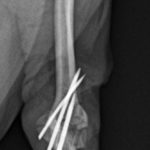

アキレス腱断裂 主治医よりアキレス腱断裂した患者さんが脚を着けなくなったので、なんとかして欲しいと連絡がありました。経関節ピンによる一時的な足根関節の仮固定とアキレス腱の縫合術により対応しました。しばらくは安静が必要です。 症例カテゴリー 放射線治療整形外科軟部組織外科脳神経外科内科腫瘍外科救急・集中治療リハビリテーション科腫瘍内科内視鏡科脳神経科呼吸器外科中医・漢方猫の腎移植循環器科